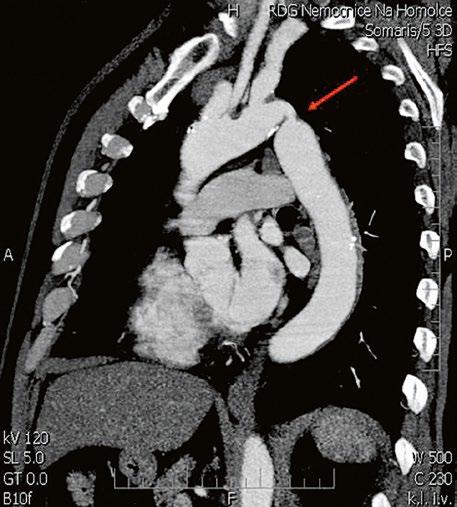

Supravalvární pulmonální stenóza a stenózy větví plicnice bývají součástí komplexních VSV (např. Fallotovy tetralogie) nebo syndromů (Williamsův syndrom, syndrom Noonanové, syndrom vrozené rubeoly, Alagillův syndrom aj.) (Obr. 45.39). Získané stenózy větví plicnice, ale i úplný uzávěr větve plicnice můžeme vidět po spojkových operacích podle BlalockaTaussigové (Obr. 45.40, Obr. 45.41). Pro zobrazení supravalvárních a periferních stenóz plicnice je optimální CT angiografie (Obr. 45.40, Obr. 45.41, Obr. 45.42, Obr. 45.43).

Obr. 45.40 CT angiografie, 8mm stenóza a deformace levé větve plicnice (šipka) po spojkové operaci podle BlalockaTaussigové v dětství LPA – levá větev plicnice, PA – kmen plicnice, RPA – pravá větev plicnice

Obr. 45.42 CT angiografie. Dilatace kmene plicnice (PA), periferní stenóza v oblasti bifurkace a odstupu pravé větve plicnice (RPA) označena šipkou, odstup levé větve plicnice (LPA) je také lehce zúžen.

Obr. 45.41 Uzávěr levé větve plicnice jako následek provedené spojky podle BlalockaTaussigové v dětství, CT angiografie

Obr. 45.43 CT angiografie, šipkou označena významná odstupová stenóza levé větve plicnice (LPA), lehčí stenóza odstupu pravé větve plicnice (RPA), kalcifikace v oblasti pulmonální chlopně